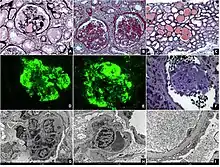

On histology, FSGS manifests as scarring (sclerosis) to segments of glomeruli; moreover, only a portion of glomeruli are affected.[7][20][21] The focal and segmental nature of disease seen on histology help to distinguish FSGS from other types of glomerular sclerosis.[21]

Diagnosis of FSGS is made by renal biopsy that includes at least fifteen serial cuts with at least eight glomeruli.[31][32] Histologic features include sclerosis (scarring) of a portion (average: 15%) of the glomerular space, with only a portion of glomeruli manifesting any sclerosis.[32]

Five mutually exclusive variants of focal segmental glomerulosclerosis may be distinguished by the pathologic findings seen on renal biopsy:[34]

Recognition of these variants may have prognostic value in individuals with primary focal segmental glomerulosclerosis. The collapsing variant is associated with higher rate of progression to end-stage renal disease, whereas the glomerular tip lesion variant has a low rate of progression to end-stage renal disease in most patients.[9] The cellular variant shows similar clinical presentation to collapsing and glomerular tip variant but has intermediate outcomes between the other two variants.[9]